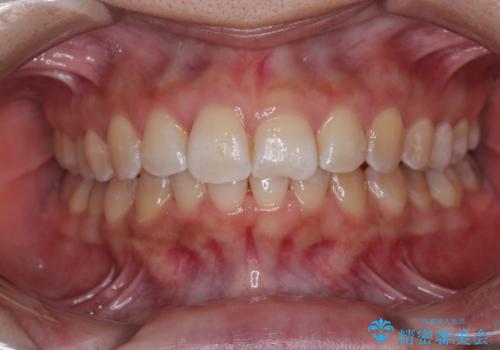

[ マウスピース矯正 ] がたがたした歯並びを治したい

担当医 大元洋佑